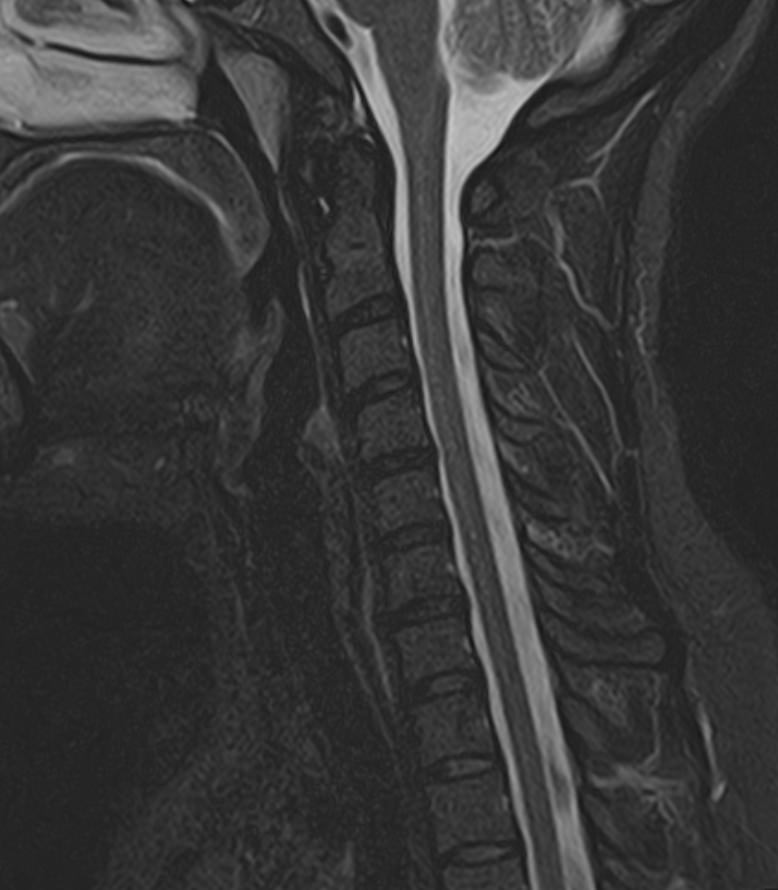

Для того, чтобы оценить состояние шейных позвонков с прилегающими тканями и одновременно визуализировать плечевой сустав, в нашей клинике выполняется комплексное обследование, включающее два протокола: МРТ шейного отдела позвоночника и МРТ плечевого сустава.

Метод МРТ позволяет оценить состояние всех анатомических областей шейного отдела позвоночника: костную структуру позвонков, спинной мозг с отходящими от него нервными корешками и окружающие мягкие ткани. Протокол обследования плечевого сустава включает оценку костной структуры, суставной капсулы, полости сустава с выстилающей его синовиальной оболочкой, связок, сухожилий, мышц и окружающих мягких тканей.

В клинике «Доступная медицина» исследование проводится на современном высокопольном томографе закрытого типа TOSHIBA VANTAGE TITAN 1,5 Тесла с превосходной  разрешающей способностью, которая обеспечивается высокой индукцией магнитного поля. Аппарат выполняет сканирование послойно в различных плоскостях и на основе этого создает 3D-изображения с высочайшей точностью и достоверностью, что позволяет эффективно ставить диагноз и назначать необходимое лечение.

• Дегенеративно-дистрофические заболевания шейного отдела позвоночника (межпозвонковые грыжи, протрузии, остеохондроз, спондилоартроз, спондилез, унковертебральный артроз, сколиоз, усиленный или выпрямленный лордоз как нарушение статической функции позвоночника).